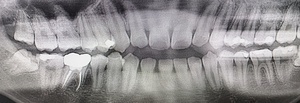

Before(下親知らずの抜歯前) 横に生えた状態で埋まっている親知らず 虫歯がある親知らず 抜歯前の骨の状態のレントゲン像

まず、親知らずと骨の中にある神経の位置、歯や周囲の骨の詳細な情報を確認するために、歯科用パノラマデジタル写真で口腔内を撮影します。撮影結果を踏まえ、抜歯方法や施術の難易度をしっかり確認しました。